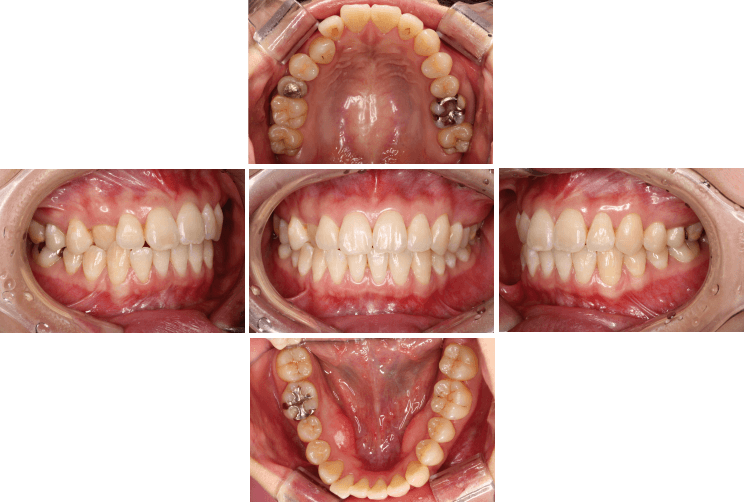

- 口腔内写真撮影

初診時のお口の中の状態を記録するため、5~6枚程度の写真を撮影させていただきます。